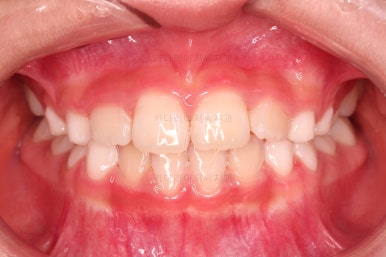

4. 마무리

부산어린이교정 키다리아저씨치과에서 앵글씨 3급 부정교합 및 반대교합이 잘 개선되었습니다.

심지어는 치열을 정교하게 맞추는 기능이 있는 장치는 아니지만, 자연스럽게 맹출 경로를 잡아줌으로써 앞니 치열도 매우 고른 양상이 되었습니다.

전후 비교해 보겠습니다.

옆라인도 아랫입술이 불룩해 보이던 양상에서 많이 좋아졌고요.

웃을 때 드러나는 치열도 좋아졌네요.

향후에는 호흡기 및 혀 위치로 인해 재발이 되지 않는지를 중점적으로 체크해 나가게 됩니다.